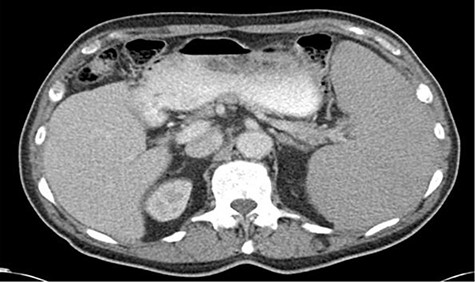

The patient underwent a computed tomography (CT) abdomen pelvis as an outpatient, revealing splenomegaly measuring 18 × 9 × 5 cm (Fig. 1). The patient was subsequently admitted to our facility for the evaluation of his anemia secondary to what was thought to be a likely hematologic malignancy. The patient underwent a bone marrow biopsy, which demonstrated hypercellularity and erythroid hyperplasia with unremarkable cytogenetic markers and no evidence of myelodysplastic syndrome.

CT abdomen and pelvis axial images demonstrating splenomegaly measuring 18.4 × 9.4 × 15.8 cm.